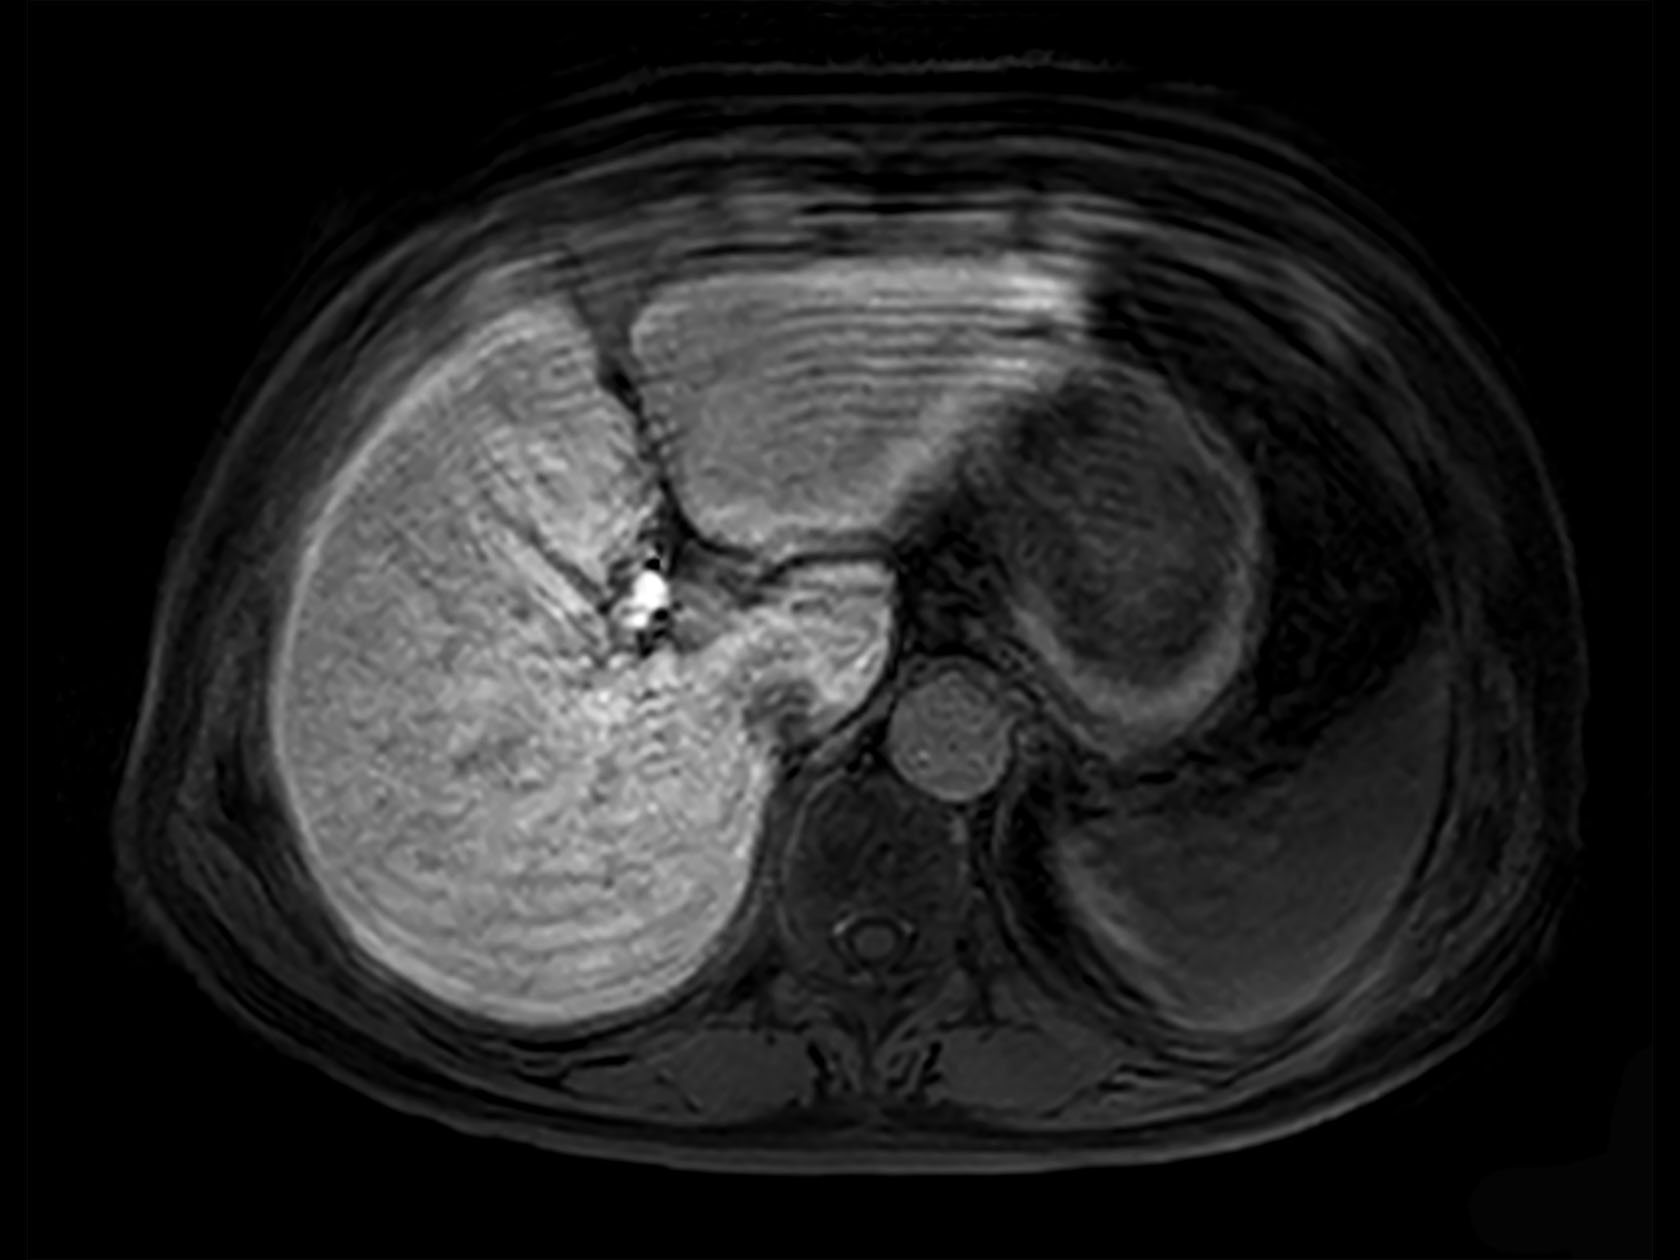

Axial 3D VANE XD (Out Phase)